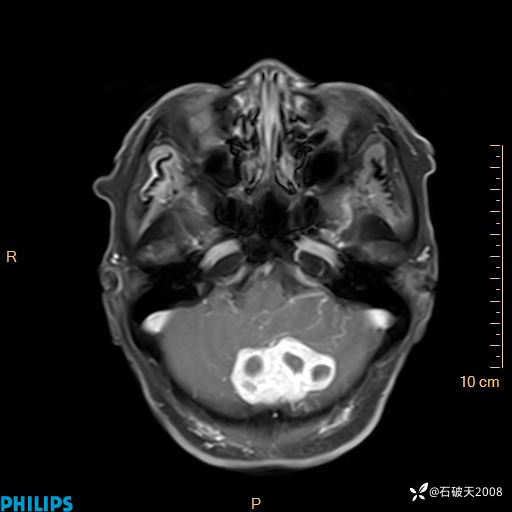

书上说这个肿瘤发生在幕下仅4.09%,你会想到它吗?(病理已公布)

女 86岁 主 诉:乏力1月

现病史:患者1月前活动出现双下肢乏力,无头晕、头痛、恶心、呕吐、肢体活动不利,休息后缓解,间断断发作,症状进行性加重,在家口服药物治疗(具体不详),效差,为进一步诊治,来我院,门诊按“乏力”收住我科,患者自发病以来,神志清,精神稍差,饮食睡眠欠佳,大小便正常,体重未见明显改变。

T2